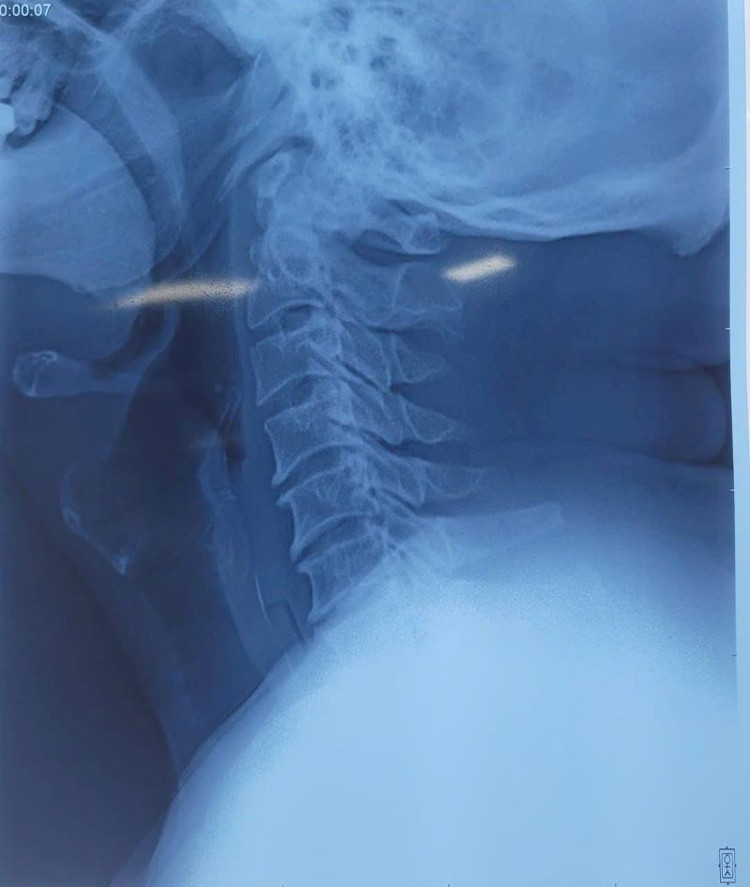

Ngày 12/8, Bệnh viện Đa khoa Hà Nam cho biết, khoa Tai Mũi Họng vừa tiếp nhận bệnh nhân T.V.T. 60 tuổi ở Tam Chúc, tỉnh Ninh Bình bị hóc viên thuốc còn vỏ cứng.

Theo bệnh nhân kể, bệnh nhân bị sốt tự mua thuốc tại hiệu thuốc về uống. Do công việc bận rộn và sơ suất, trong khi uống cả liều thuốc, bệnh nhân uống cả viên thuốc còn vỏ cứng được cắt ra từ vỉ thuốc. Ngay sau đó, người bệnh xuất hiện nuốt đau, nghẹn, nuốt vướng nhiều ở vùng ngực.

BSCKII Nguyễn Thị Tú Uyên chia sẻ, người bệnh khi tự mua thuốc tại các hiệu thuốc thường được chia liều với nhiều loại thuốc cắt nhỏ nhưng còn nguyên vỏ cứng. Trong quá trình uống thuốc nếu không chú ý, bệnh nhân sẽ uống thuốc mà không bỏ phần vỏ thuốc.

Việc này rất nguy hiểm vì viên thuốc có vỏ cứng sẽ không tan rã, phần cạnh sắc của viên thuốc sẽ cắm vào thành ống tiêu hóa (hay gặp nhất là thực quản) gây ra rách, thủng thực quản. Nguy hiểm hơn nữa nếu vị trí cắm của viên thuốc sát các mạch máu lớn của vùng ngực như động mạch chủ ngực, có thể gây rách thành động mạch.